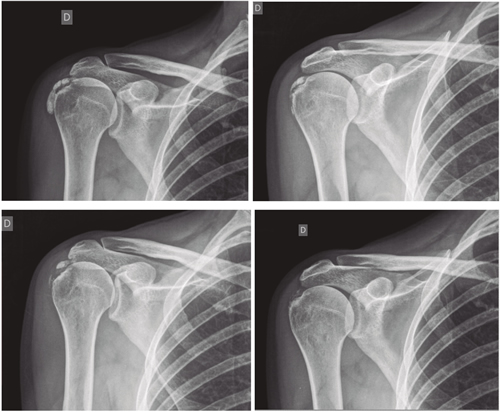

Figura 1

Figura 2

Figura 3

Figura 4

Figura 5

Figura 6